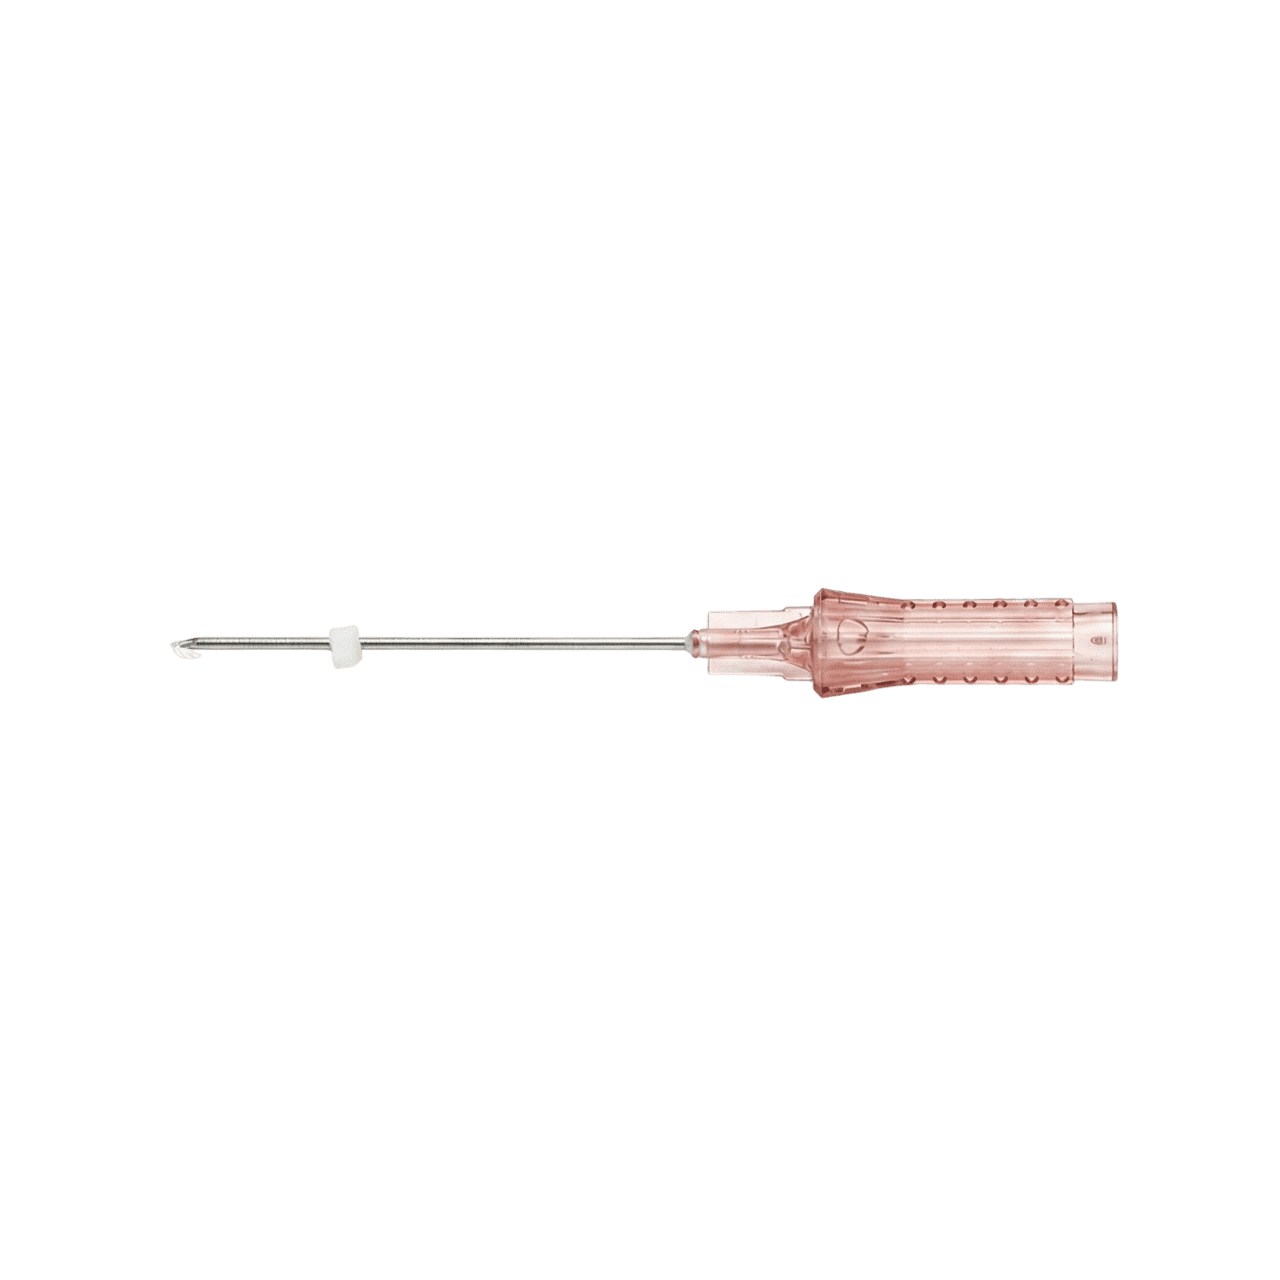

Equipment/Laser

We provide effective and safe treatments using verified cutting-edge medical equipment and lasers.